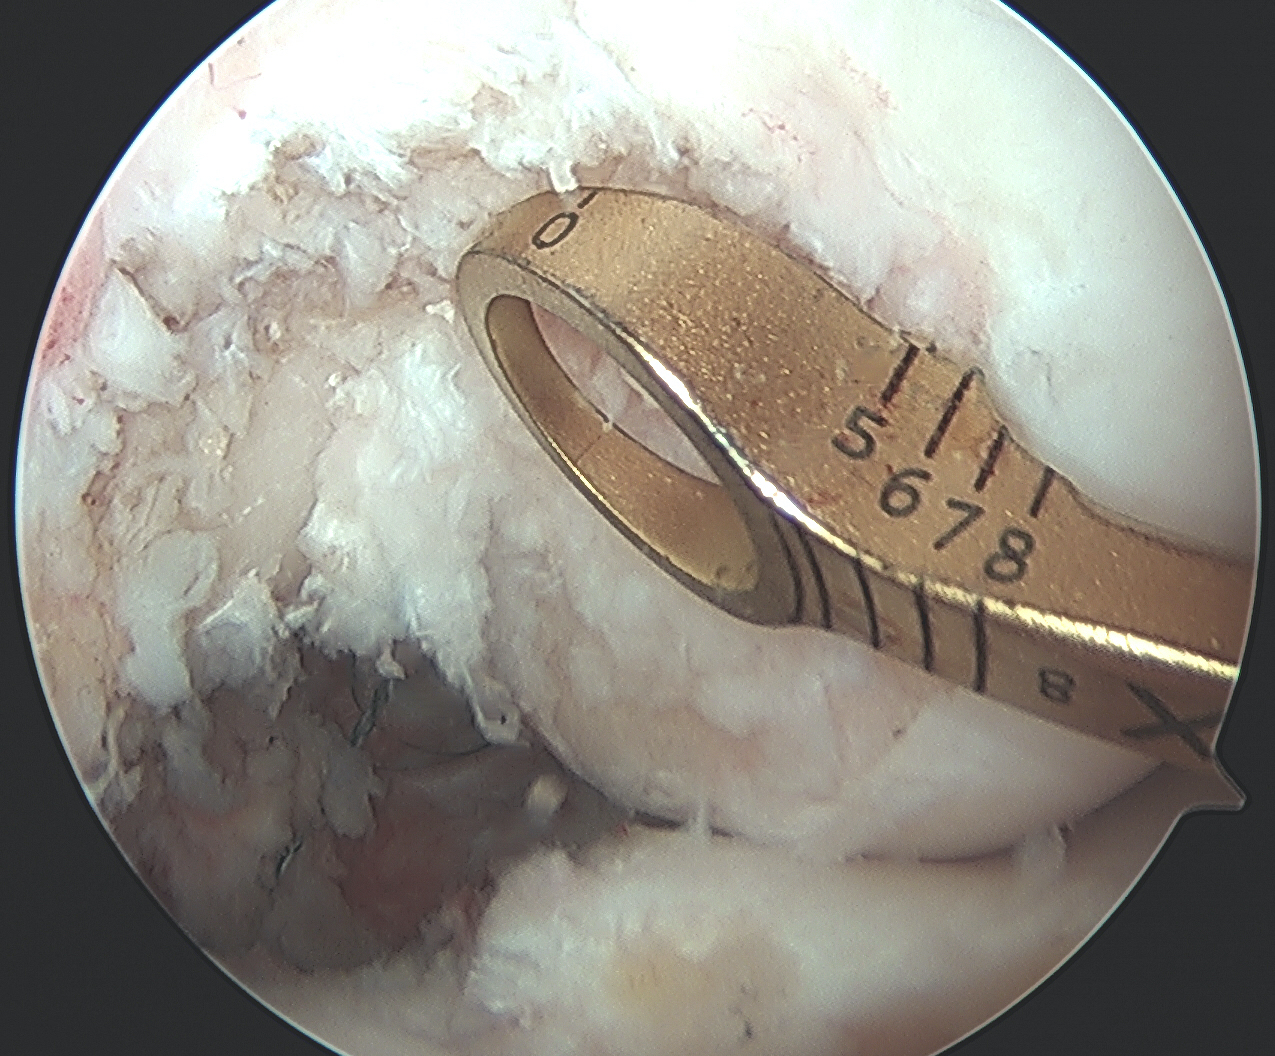

PCL facet 1PCL tibial tunnel

PCL tibial facet                                                           Tibial tunnel beath pin

Clear tibial origin

Need adequate visualisation of the PCL facet

- down at least 1 - 2 cm below articular surface

- combination of shaver and electrocautery

- usually need to release some of the capsular insertion onto posterior tibia